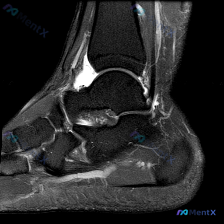

踝关节MRI见广泛软组织积液,这个分析思路帮你理清鉴别方向

看到这份踝关节MRI读片资料,整理出来和大家分享分析思路。

病例基本影像信息

这是踝关节MRI轴位T2加权图像,先给大家梳理影像上的基本发现:

- 骨骼结构:距骨、外踝(腓骨远端)、内踝(胫骨远端后部)骨皮质连续,无骨折或骨质破坏,骨髓信号均匀,无异常骨髓水肿

- 肌腱与韧带:腓骨长/短肌腱、跟腱、内侧胫骨后肌腱等走行清晰,跟腱形态信号正常;可辨认外侧副韧带复合体(距腓后韧带)结构

- 核心异常发现:

- 踝关节胫距关节腔内可见明显高信号影,提示关节积液

- 关节周围软组织存在广泛弥漫性高信号,尤其前外侧、后内侧区域片状分布,边缘模糊,符合软组织水肿

- 距腓后韧带增粗、信号增高,和周围水肿边界欠清晰

初步分析思路

T2加权上的广泛高信号提示这是急性期的炎症渗出/水肿改变,不是慢性纤维化病变,首先考虑是急性损伤或炎症反应导致的软组织积液。